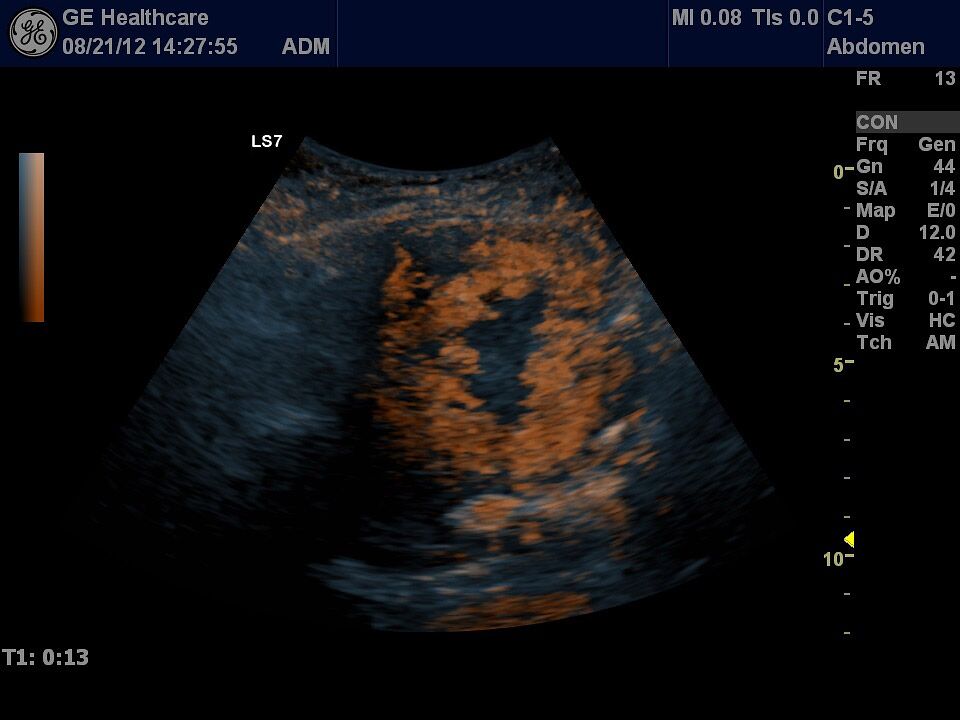

Die Ultraschall-Untersuchung ist mit Recht eine der wichtigsten und häufigsten Untersuchungsmethoden. Der Ultraschall ist ein bildgebendes Verfahren. Er erlaubt, von außen in den menschlichen Körper hinein zu sehen. So können die inneren Organe enorm detailreich und aussagekräftig untersucht werden. Vor allem die Weichteile wie Leber, Bauchspeicheldrüse, Galle, Niere oder Milz, die beim Röntgen nur schlecht zu sehen sind, können ausgezeichnet dargestellt werden.

Die Ultraschalluntersuchung ist ein sehr schnelles und leistungsstarkes Diagnoseverfahren. Dabei kann der Arzt Abläufe im Körper in Echtzeit sehen! Er hat keine Momentaufnahme vor sich, wie auf den Bildern des Röntgens oder der Computertomographie, sondern ein bewegtes Bild. Um zum Beispiel die Darmbeweglichkeit oder Organdurchblutung darzustellen, ein großer Vorteil. Da Sie als Patient dabei nicht in einer Röhre liegen, sondern ihr behandelnder Arzt neben Ihnen ist, kann ganz gezielt untersucht werden; dabei Beschwerdepunkte gezeigt, Befunde direkt erläutert und das weitere Vorgehen abgesprochen werden.